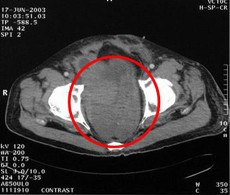

患者病情:左下腹壁脂肪肉瘤2次術(shù)后復(fù)發(fā),療前132.9cm2。治療方案:瘤內(nèi)注射今又生1-2×1012VP/次/周×14;熱療40MHz 42-43°C,1次/周×22,今又生注射后 3天進(jìn)行;放療60Gy結(jié)果:療后腫瘤大小無改變,但50%以上低密度區(qū)(LDA),治療后3周,8kg腫塊切除,隨訪50個(gè)月健康生存。

治療前

治療后